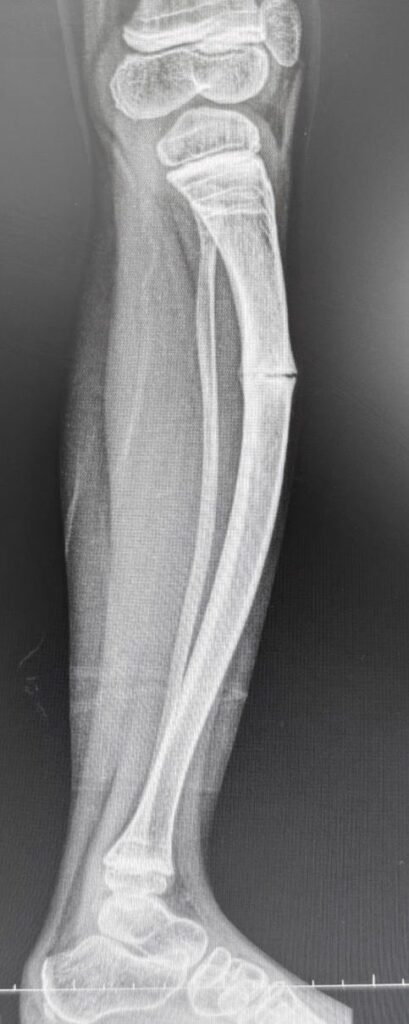

O Hospital 22 de Outubro alcançou um grande marco no último sábado (20), ao realizar a primeira cirurgia da região para correção de deformidade óssea em um paciente de 8 anos com Osteogênese Imperfeita tipo 5. O procedimento, que envolveu uma dupla osteotomia da tíbia, foi realizado pelo ortopedista e traumatologista, Dr. Guilherme Maretti Franco De Campos, e pela Dra. Michelle Cardoso, especialista em deformidades ósseas da AACD.

O paciente, que sofria de múltiplas fraturas recorrentes e apresentava uma grave deformidade na perna esquerda, foi tratado com a implantação de uma haste intramedular telescopada Fassier-Duval. Esse dispositivo, que se ajusta ao crescimento do osso, oferece suporte e estabilidade, prevenindo fraturas à medida que a criança cresce.